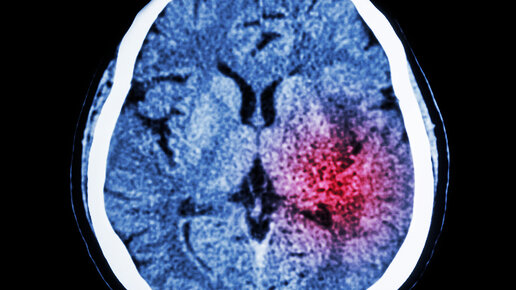

Обновленный материал по теме - Черепно-мозговая травма Черепно-мозговая травма – это понятие, которое объединяет в себе механические повреждения головного мозга различной степени тяжести. Стоит отметить, что в данное понятие входят и непосредственные повреждения самого черепа, а также травмы тканей мозга, мозговых оболочек, черепных нервов и т.п. В современной медицине существует довольно подробная классификация черепно-мозговых травм. Врачи выделяют несколько основных типов ЧМТ в соответствии с...

Механические повреждения возникают при прямом физическом воздействии — ударах, сдавлениях или разрывах нервной ткани. Черепно-мозговая или спинномозговая травма не только разрушает нейроны и их отростки, но и запускает каскад вторичных процессов: отек, нарушение кровоснабжения и нейровоспаление. Главная проблема восстановления — природные ограничения ЦНС. В отличие от периферических нервов, нейроны головного и спинного мозга почти не регенерируют. Виной тому особые белки (Nogo-A, MAG, Omgp), которые...